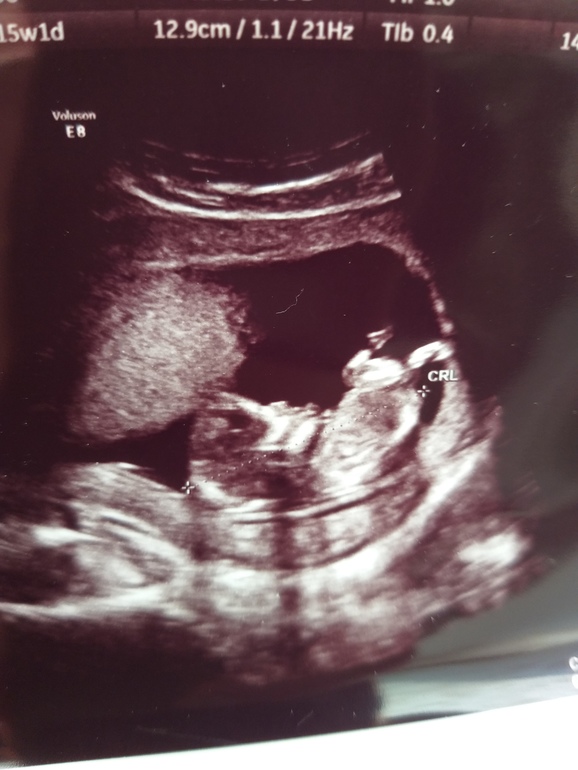

Это ведь наш Пэрсик?))

Пол малышаЭх, не выдержала душа поэта! Достала узи в 13,6 и стала разглядывать...

Вроде девочка, вон он пэрсик...

Эх, не выдержала душа поэта! Достала узи в 13,6 и стала разглядывать...